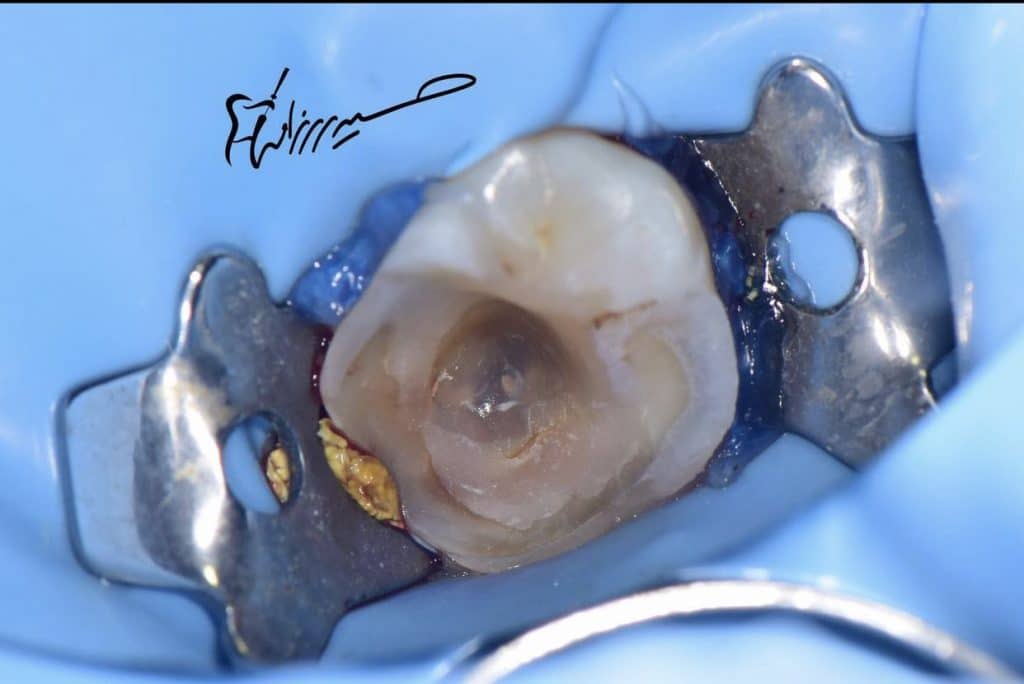

Ids and resin coat + ever x posterior

Endocrown(overlay!) prep

Prep and isolation